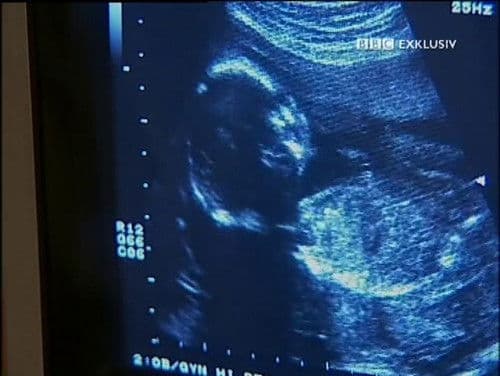

Child of Our Time S1

Babies